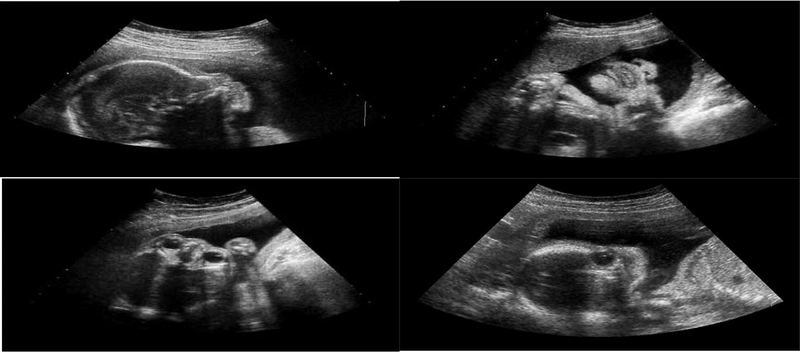

Khi thăm khám sản - phụ khoa rất nhiều chị em đều được các bác sĩ chỉ định cho làm siêu âm đầu dò để hỗ trợ chẩn đoán. Tuy nhiên, rất nhiều không hiểu về kỹ thuật này cũng như lý do vì sao phải làm kỹ thuật siêu âm đầu dò. Cùng Nhà Thuốc Long Châu tìm hiểu về kỹ thuật siêu âm đầu dò nhé!

Siêu âm đầu dò là kỹ thuật chẩn đoán hình ảnh được sử dụng rất rộng rãi với độ chính xác khá cao, thường được sử dụng để thăm dò và chẩn đoán đối với lĩnh vực sản - phụ khoa. Với việc đưa thiết bị đầu dò siêu âm từ 2 - 3 inch vào âm đạo và sử dụng sóng siêu âm để kiểm tra những bất thường về vị trí, hình thái, cấu trúc của hệ sinh dục.

Thứ tự thăm dò thường đi từ ngoài vào trong theo thứ tự: Âm đạo, cổ tử cung, tử cung hay dạ con, ống dẫn trứng và buồng trứng. Từ đó, giúp ích cho bác sĩ chẩn đoán xác định bệnh nhanh chóng và chính xác.

Do đây là kỹ thuật tiếp cận sâu và bên trong của cơ thể nên siêu âm đầu dò đem đến hình ảnh cụ thể và chính xác hơn mà siêu âm qua thành bụng ít khi phát hiện được nhất là ở vùng tiểu khung, trực tràng do bình thường bị cản trở nhiều bởi xương chậu.